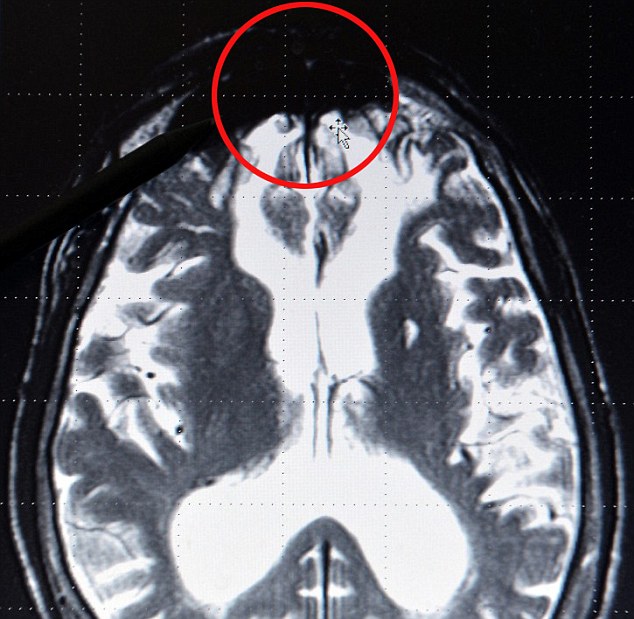

Depois de analisar os cérebros de criminosos violentos, o neurologista alemão Gerhard Roth diz que encontrou uma área no lobo frontal que denominou “mancha do mal”. Ela é vista como uma área mais escura nos aparelhos de ressonância magnética.

No entanto, as imagens do cérebro dessas mesmas pessoas possuíam a mesma “mancha escura” no cérebro, o que pode significar que alguns criminosos teriam uma “predisposição genética” para a violência.